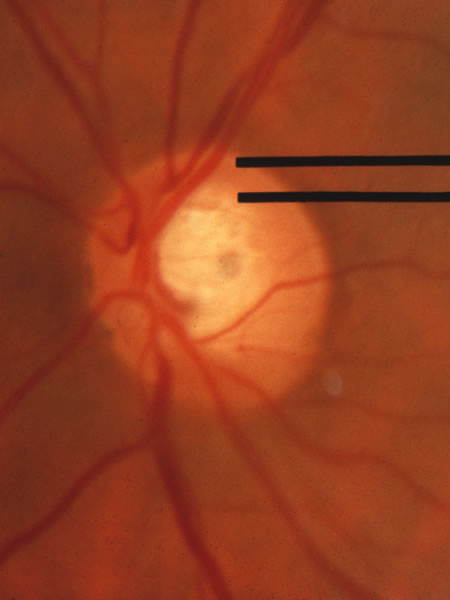

Fig. 2. Normal optic nerve configuration. Notice that the height (H) of the disc is greater than the width (W). The width of the neuroretinal tissue (A) is also greater in the vertical meridian than in the nasal and temporal meridians (B); thus, the physiologic cup is round.

Fig. 3. Normal disc untilted, taller than it is wide. The neuroretinal tissue in the upper and lower sectors is more abundant in these sectors than others, so the central cup is round. A narrow white line marks the disc boundary and represents the lip of sclera that in humans almost universally separates the choroid from the optic disc tissue around the entire circumference.